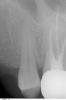

Helen_V Опубликовано 6 февраля, 2008 Автор Поделиться Опубликовано 6 февраля, 2008 (изменено) Огромное спасибо всем ответившим в тему!! Извините за задержку снимков - только сегодня удалось их получить - на прошлой неделе секретарь никак не хотела пересылать их под соусом "дайте email врача, мы сами отправим". Снимок 3 - правее зуба с коронкой как раз он, последний в верхнем левом. Судя по снимку, у меня еще и зуб мудрости лезет. Это два других. Я попросила сделать эти снимки, так как было ощущение, что болит вся сторона. Рядом с короночным зуб, который тоже непонятно почему предыдущая дентист решила "полечить" - не беспокоил абсолютно. Надеюсь, с ним все в порядке? А вот левее был тот многострадальный зубик, в котором она удалила нервы (хотя не беспокоил и я тогда обращалась, потому что проблемы были с другой стороны), а через две недели я ела йогурт с мюслями и зуб раскололся надвое. Дантист отколола часть зуба, засунула ватку (которая вылетела через пару дней) и уехала в отпуск на две недели. А по приезду развела руками, что сделать ничего не возможно, потому как десна заросла. Я ей говорила, что видела на русских сайтах работы дантистов, которым удавалось сохранить зуб. Чтобы она попробовала что-то сделать. Но поняла, что она не хотела рисковать. и обращение к другому врачу не помогло - время было упущено. пришлось его удалять. Вот такая история. невеселая. А муж вчера еще раз спрашивал дантиста, какого он вообще полез в этот зуб, если не беспокоил. он сказал, чтобы обновить пломбу (здесь любимая песня дантистов - "надо переделать все пломбы, что вам делали в бывшем Союзе" (даже если делали 4 года назад и ничего не беспокоит - "все равно плохо")). То есть получается никакого кариеса не было? Более того, он ведь даже не уведомил меня, что он собирается делать. А потом типа я жаловалась на боль, что типа пломба близко к нерву. А когда в третий раз приехали, он решил поставить временную пломбу понаблюдать, но увидел, что "слишком глубоко дырка". Потому надо удалять нерв. Но вроде заверил, что засунул лекарство, не мышьяк. Но если поставить времянку, через полгода все равно прийдется удалять нерв. Неужели уже нельзя спасти никак зуб?? оставить нервы? Изменено 6 февраля, 2008 пользователем Helen_V Ссылка на комментарий

kromanion Опубликовано 6 февраля, 2008 Поделиться Опубликовано 6 февраля, 2008 Helen!По Вашему описанию лечения возможно предположить,что зуб уже имел внутреннюю трещину(учитывая то,что Вы давно замечаете скрежетание зубами).Судя по снимкам,травмирование зубов должно быть,т.к. есть признаки начального поражения костной ткани примерно в пришеечной области.Очень часто резкая болезненность при лечении(даже с анестезией) бывает при трещинах или переломах корней.И чаще всего это бывает с верхними "шестерками",имеющими один(из трех) тонкий и изогнутый корень.И проявиться это может именно при лечении каналов,т.к. для доступа к нерву убирается основная масса твердых тканей,закрывающих доступ к этой трещине.Плюс окклюзионная нагрузка ослабленного зуба-и зуб раскалывается при приеме мягкой пищи.До удаления возможно сделать компьютерную томографию.Иногда помогает удаление только одного сломанного корня,а зуб остается на двух достаточно крепких корнях.Но это вряд ли будут делать в Канаде.Для сохранения остальных зубов, реставраций и коронок на них желательно изготовить защитную каппу,а также проверить равномерность смыкания зубов,т.к. возможно из-за выступания или проседания каких-либо из них у Вас появилось скрежетание зубами(возможна еще нейрогенная причина развития скрежетания).Изменения прикуса должны быть-у Вас есть удаленные зубы.Желательно грамотное протезирование.Удачи! Ссылка на комментарий